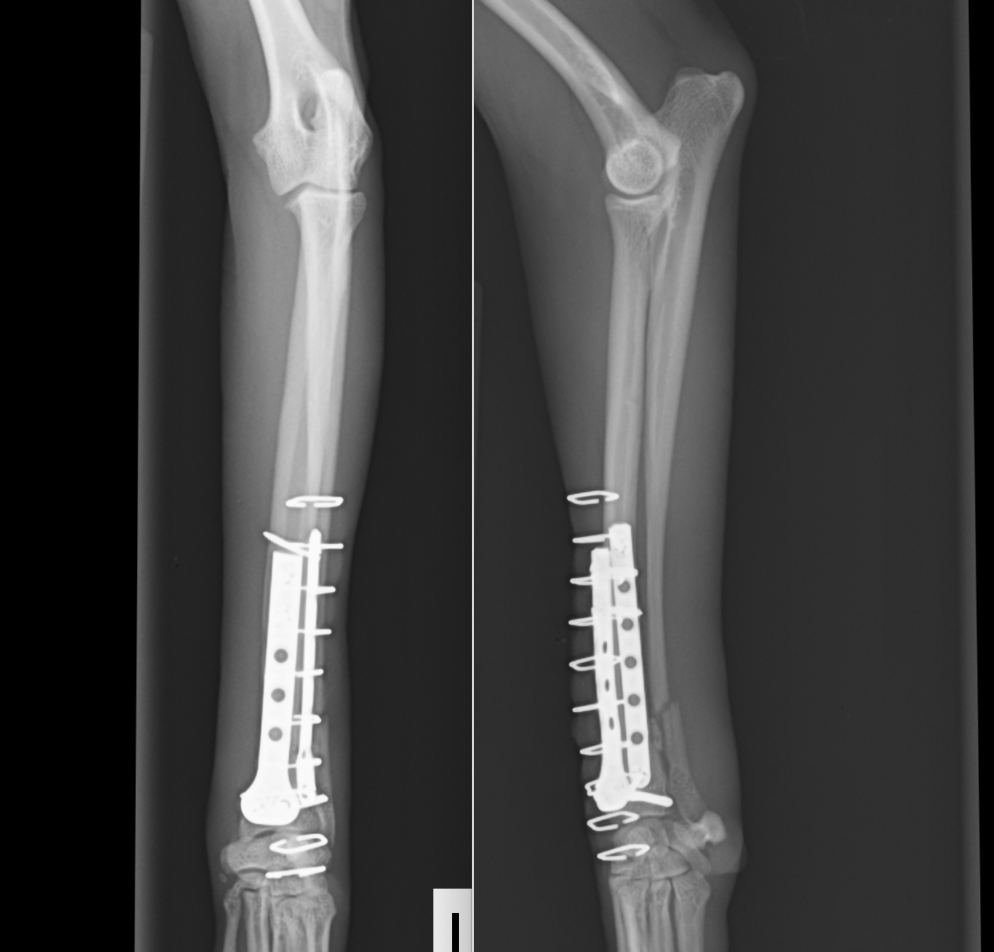

今回の手術後の写真です。非常に長いプレートが入っているのは、手術して再骨折があった場合にはもとのプレートよりも長いプレートを入れる必要があるからです。また、骨が痩せて細くなっているケースが多いので術後も注意が必要です。

術後レントゲンです。橈骨全域に渡ってプレートが入っています。近位は少し外側に曲がっているため、最初からプレートを曲げています。術後2日目には患肢を使っての歩行が可能でした。また、キャスト(ギプス)も使わないので、ストレスなく生活が可能です。術後1ヶ月半ほどで正面のプレートを抜去しています。

この子もプレートが破綻して2回めの手術をしているため、プレートが長くなっています。

術後経過は順調で2ヶ月ほどで正面のプレートを抜去しました。